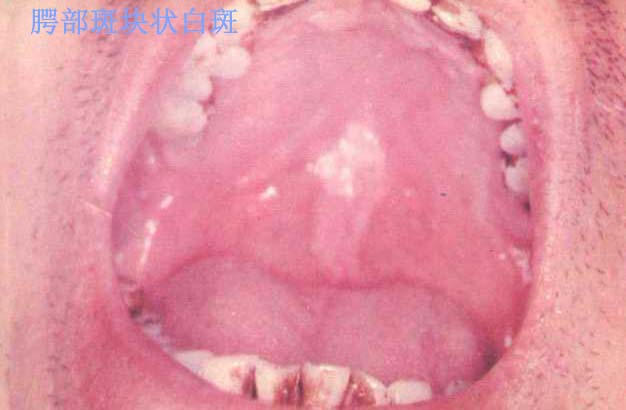

口腔黏膜白斑